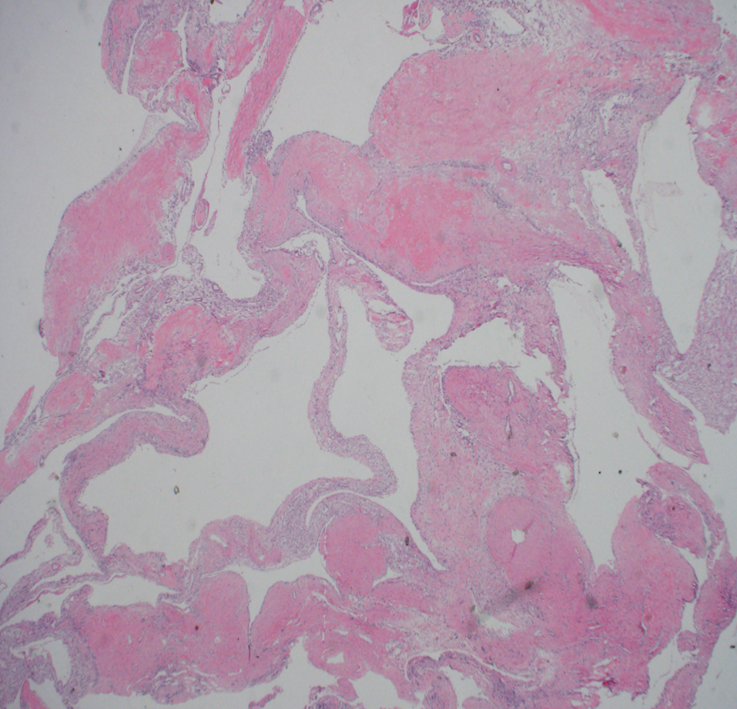

Renal tumor grading

Case ID: 653